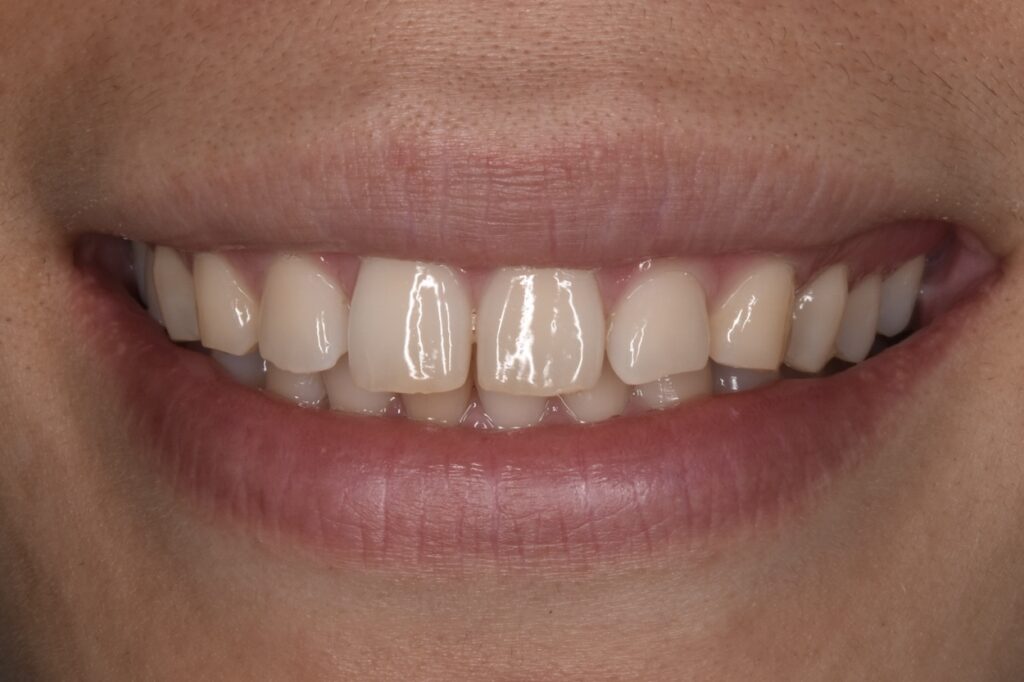

すきっ歯の改善を矯正治療でおこなった例です

モニター1 インビザラインライトプランで治療 治療期間14週間(約3・5ヶ月)

治療後